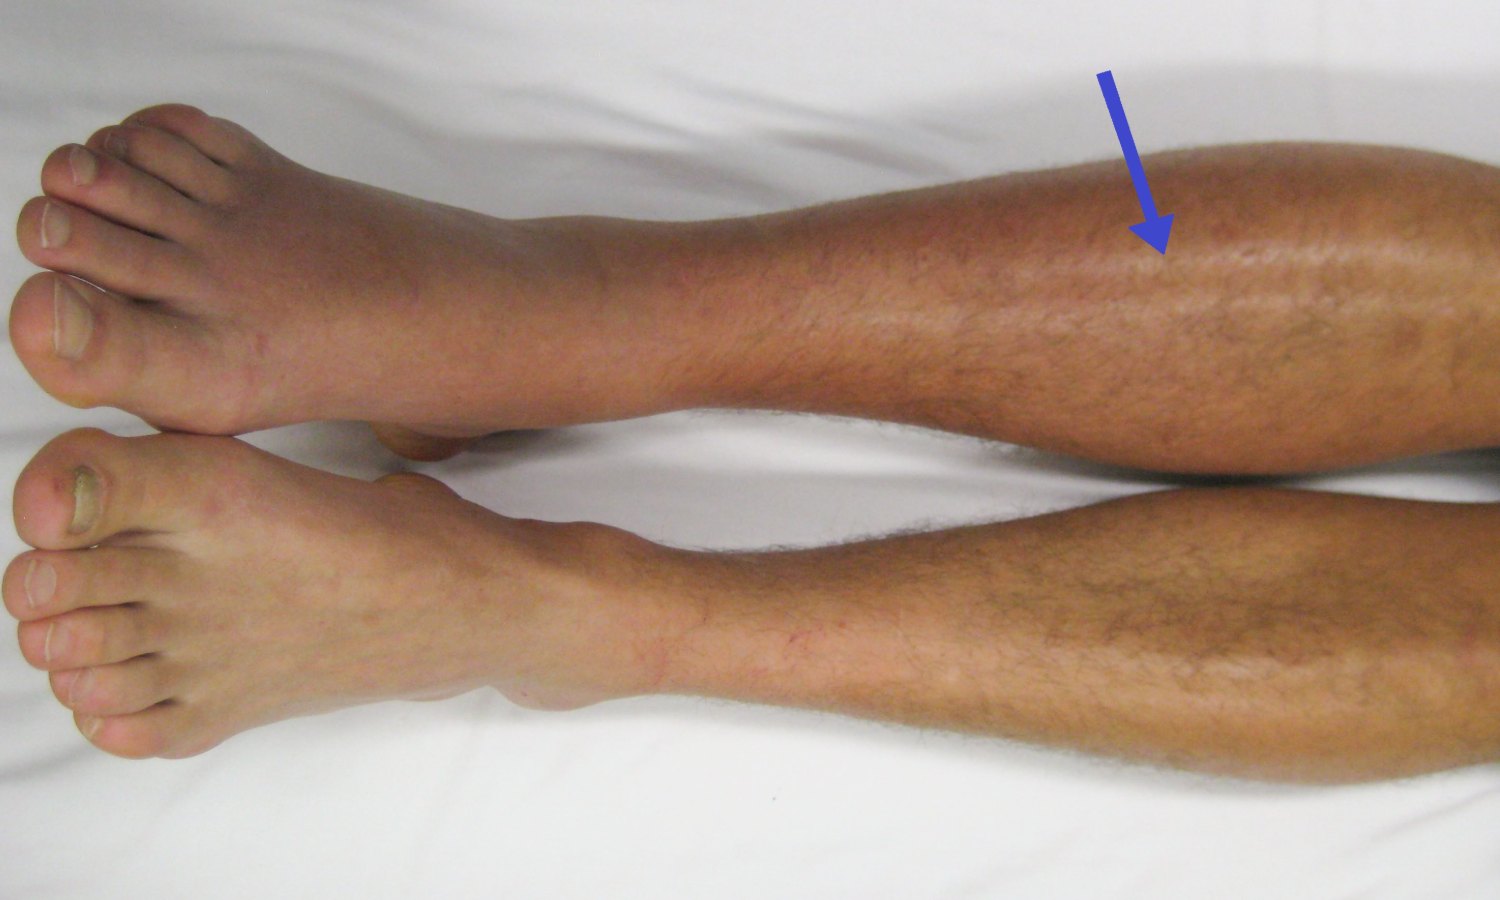

U nastavku sledi slika koja pokazuje moguć izgled tromboze noge:

Izgled noge može ukazivati na lokalizovano oticanje sa zategnutom i sjajnom kožom, a površinske vene ponekad postaju vidljivije zbog otežanog odvođenja krvi.

U težim slučajevima otok može biti izražen, sa osećajem težine i smanjenom pokretljivošću.

- Otok jedne noge: Najčešće zahvata potkolenicu ili butinu, a razlika u obimu između nogu može biti primetna.

- Crvenilo ili promena boje kože: Koža može biti crvenkasta ili blago modra.

- Povećana toplota kože: Zahvaćeno područje može biti toplije u odnosu na drugu nogu.